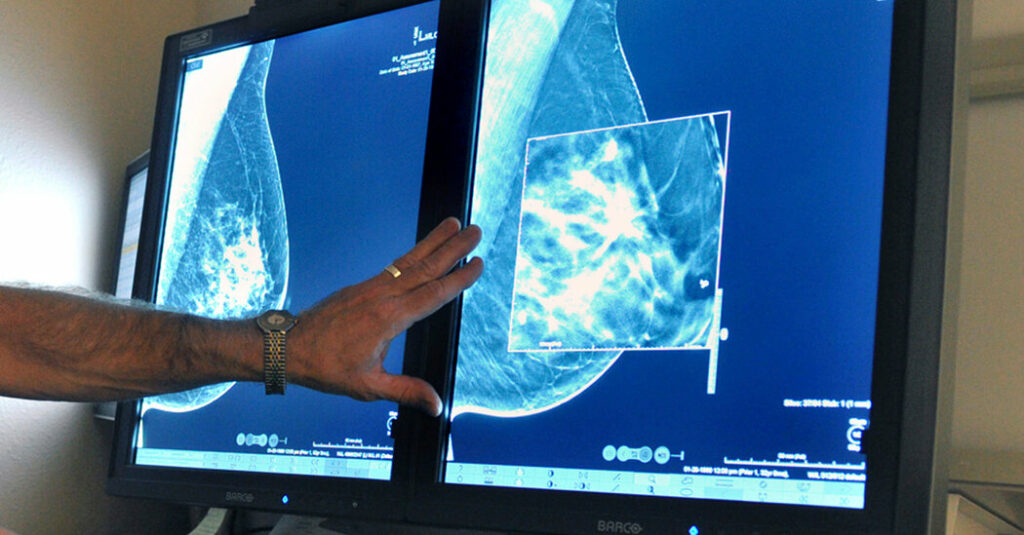

The U.S. Preventive Services Task Force, a panel of experts that issues guidelines about preventive care, has recommended all women start routine breast cancer screening at 40, instead of by 50, the previous recommendation.

The panel continues to advise spacing the screenings at two-year intervals, although some other medical organizations endorse annual mammograms.

The panel based its advice on recent, more inclusive science about breast cancer in women under 50. Although no new clinical trial data were available — and only one older trial included a significant proportion of Black women — the panel commissioned a review of screening strategies and modeling studies to come to its conclusions.

When the task force makes recommendations, it tries to balance the benefits of mammography — lives saved — with the potential harms. Those include false-positive results that cause anxiety and lead to additional testing and invasive procedures, as well as overdiagnosis — the possibility that women will be subjected to treatment for “indolent” tumors that are slow-growing and would never become life-threatening. Mammograms also expose the breasts to radiation.

Mammograms save lives, but the panel’s research found no benefit to annual mammograms over biennial scans. Annual mammograms were no better at detecting Stage 2 cancers and other dangerous tumors, they concluded. Modeling studies estimated that biennial screenings offered a better benefit-to-harm ratio.

The task force’s review of screening strategies indicated the change could increase the survival rate by almost 20 percent. Over all, biennial screening starting at 40 and continuing until age 74 will avert 1.3 additional breast cancer deaths per 1,000 women, compared with screening that starts at 50.